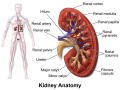

Blausen 0592 KidneyAnatomy 01.png

Lisa

20:17, 3 August 2016

1,024 × 768; 635 KB